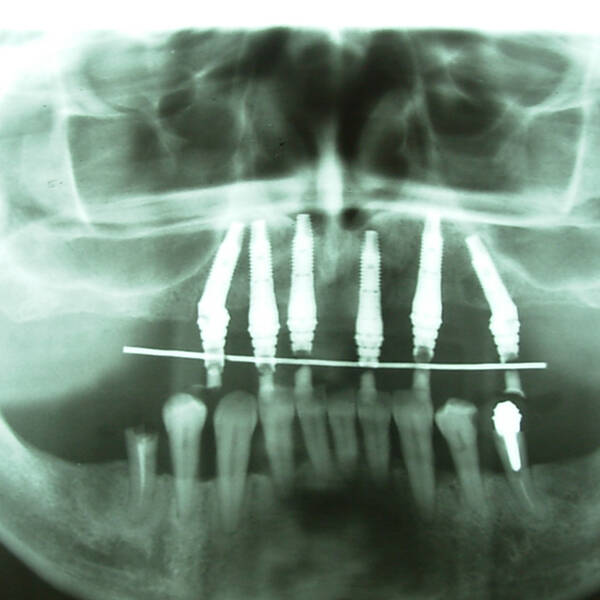

Na Clínica Pontes Odontologia, somos referência em implantes dentários em Fortaleza, oferecendo tratamentos de alta qualidade e tecnologia de ponta. Os implantes dentários são estruturas de titânio posicionadas cirurgicamente no osso maxilar ou mandibular para substituir as raízes dos dentes ausentes. Essa técnica permite a fixação de próteses personalizadas, restaurando a função mastigatória, a estética e a autoestima dos nossos pacientes.

Utilizamos a tecnologia CAD CAM, um sistema avançado que possibilita a confecção precisa das próteses dentárias diretamente sobre os implantes. Esse método inovador garante um ajuste perfeito, um resultado estético superior e proporciona muito mais conforto e durabilidade. Com o CAD CAM, nossos pacientes contam com um processo mais rápido e previsível para alcançar o sorriso desejado.